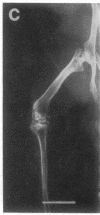

Studies were carried out on a line of transgenic mice that expressed an internally deleted COL2A1 gene and developed a phenotype resembling human chondrodysplasias (Vandenberg et al. 1991. Proc. Natl. Acad. Sci. USA. 88:7640-7644. Marked differences in phenotype were observed with propagation of the mutated gene in an inbred strain of mice in that approximately 15% of the transgenic mice had a cleft palate and a lethal phenotype, whereas the remaining mice were difficult to distinguish from normal littermates. 1-d- and 3-mo-old transgenic mice that were viable showed microscopic signs of chondrodysplasia with reduced amounts of collagen fibrils in the cartilage matrix, dilatation of the rough surfaced endoplasmic reticulum in the chondrocytes, and decrease of optical path difference in polarized light microscopy. The transgenic mice also showed signs of disturbed growth as evidenced by lower body weight, lower length and weight of the femur, decreased bone collagen, decreased bone mineral, and decreased resistance of bone to breakage. Comparisons of mice ranging in age from 1 d to 15 mo demonstrated that there was decreasing evidence of a chondrodysplasia as the mice grew older. Instead, the most striking feature in the 15-mo-old mice were degenerative changes of articular cartilage similar to osteoarthritis.